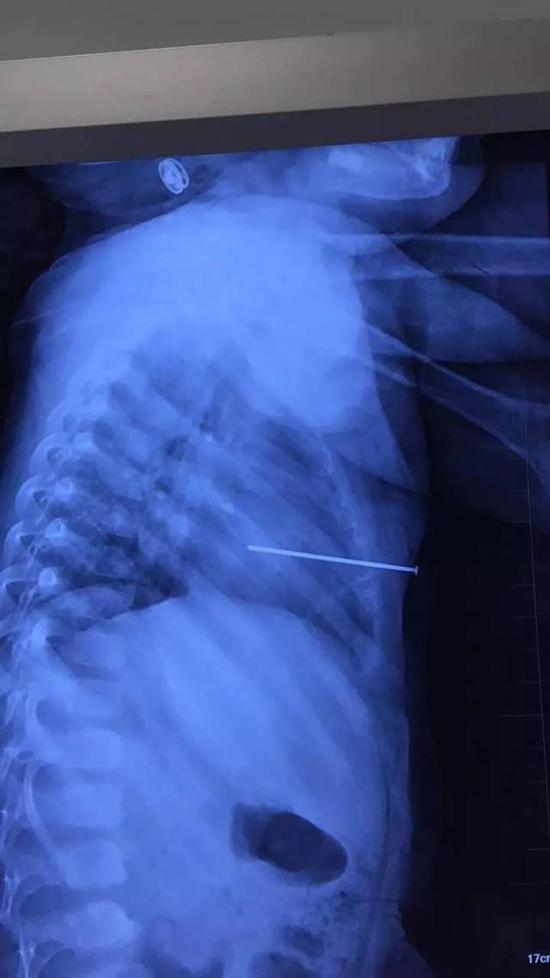

工地气钉枪走火3cm钢钉射入工人右肺险丧命

图片尺寸1024x1366